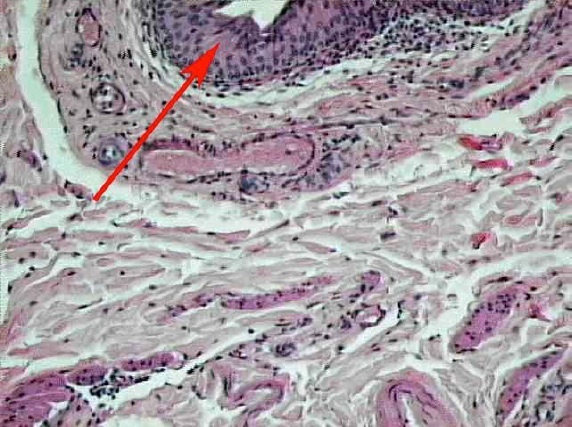

Cardiac muscle